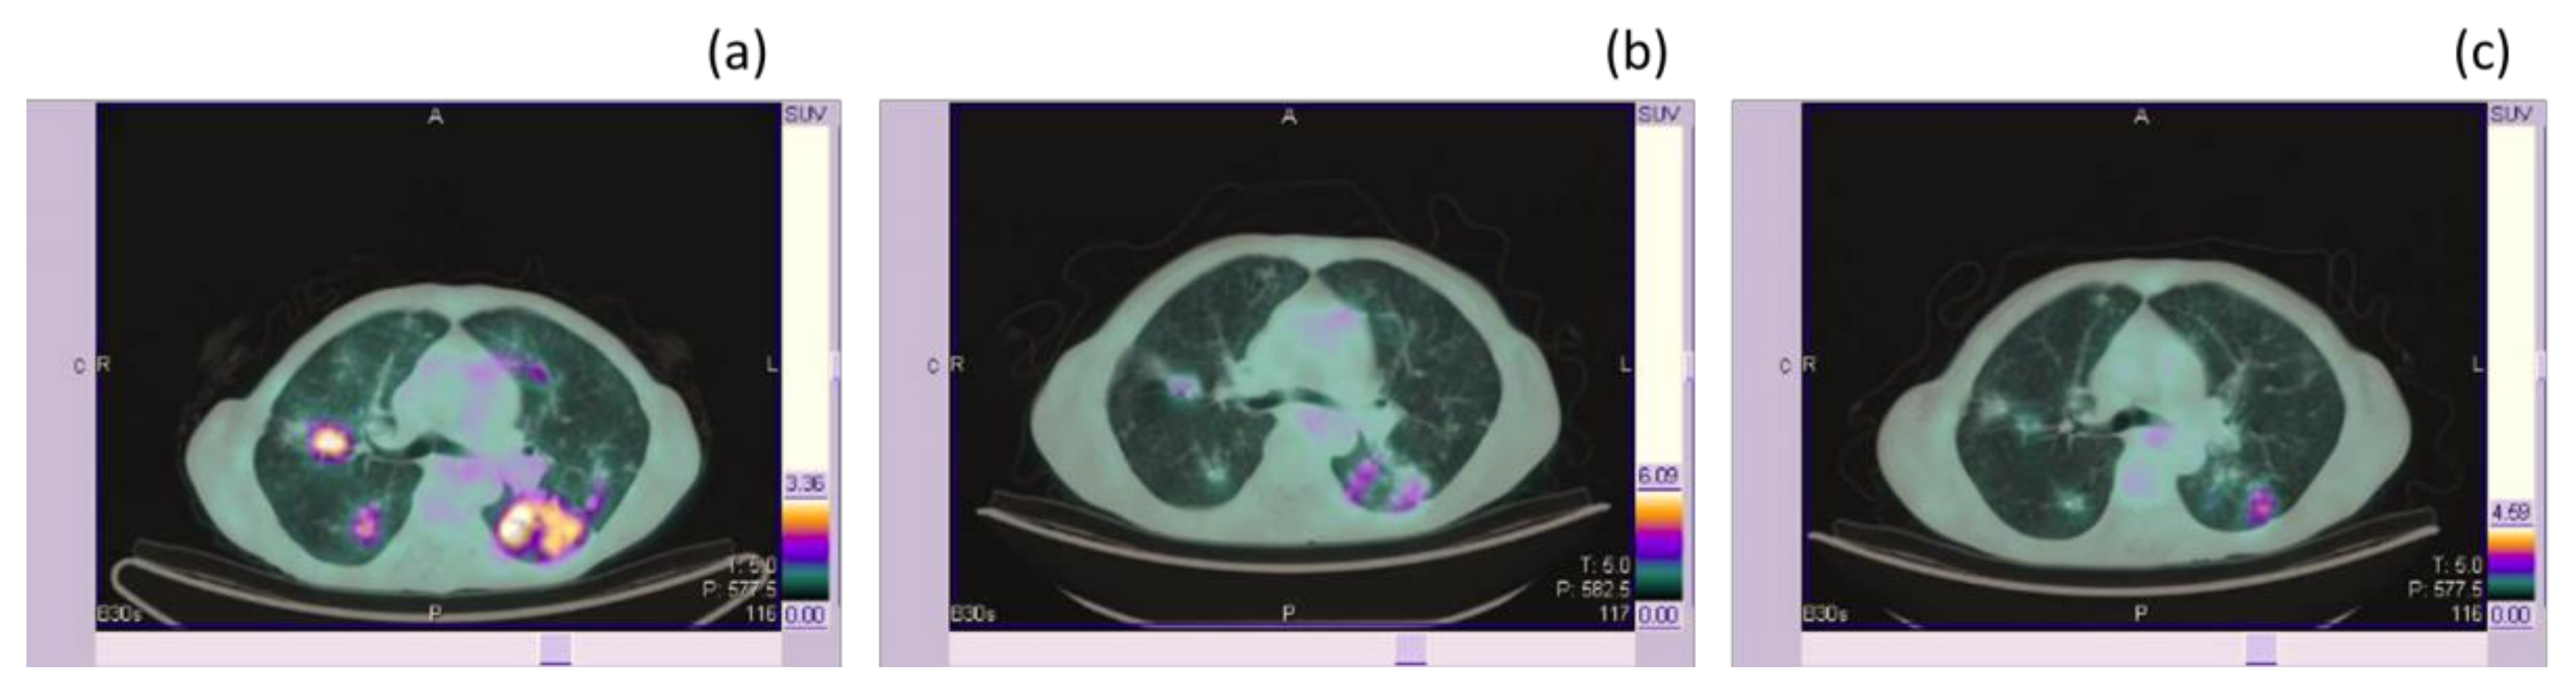

- Rossi, G.; Bauckneht, M.; Genova, C.; Rijavec, E.; Biello, F.; Mennella, S.; Dal Bello, M.G.; Cittadini, G.; Bruzzi, P.; Piva, R.; et al. Comparison between 18F-FDG-PET- and CT-based criteria in non-small cell lung cancer (NSCLC) patients treated with Nivolumab [published online ahead of print, 2019 Dec 5]. J. Nucl. Med. 2020, 61, 990–998. [Google Scholar] [CrossRef] [PubMed]

| Rossi et al. [51] | prospective | 72 patients with advanced NSCLC. | To compare the evaluation of first response to Nivolumab by means of CT-based criteria with respect to [18F]FDG PET response criteria in NSCLC patients. | Patients underwent CT scan and FDG-PET at baseline and after 4 cycles (first evaluation). Response was evaluated with CT scan by means RECIST 1.1 and IrRC and with FDG-PET by means of PERCIST and imPERCIST criteria. The concordance between CT- and PET-based criteria and the capability of each method to OS were evaluated. | A low concordance between CT- and PET-based criteria was observed. Looking at OS, IrRC were more reliable to distinguish responders from non-responders. However, thanks to the prognostic value of partial metabolic response assessed by both PERCIST and Immuno-PERCIST, PET-based response maintained prognostic significant in patients classified as progressive disease on the basis of IrRC. | The added prognostic value of the metabolic response assessment, potentially improving the therapeutic decision-making was suggested. |